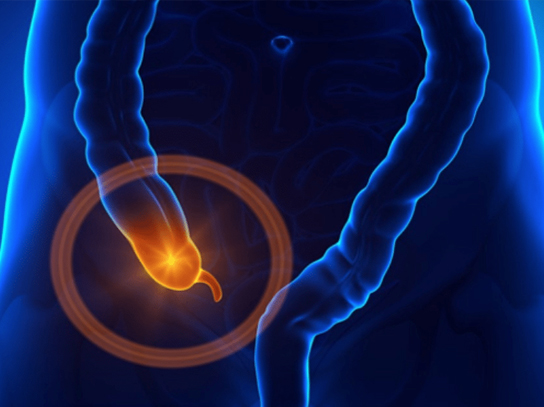

A apendicite é uma inflamação do apêndice cecal, um órgão tubular fino em forma de dedo que se projeta do cólon, no lado inferior direito do abdômen.